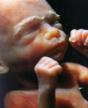

De groei.

Week 25:

Het kindje heeft het heel erg naar zijn zin in zijn kleine beschermde omgeving.

Het maakt koprollen door het vruchtwater dat het een lieve lust is.

Het kindje is nu ca. 32 cm en weegt ca. 650 gram.